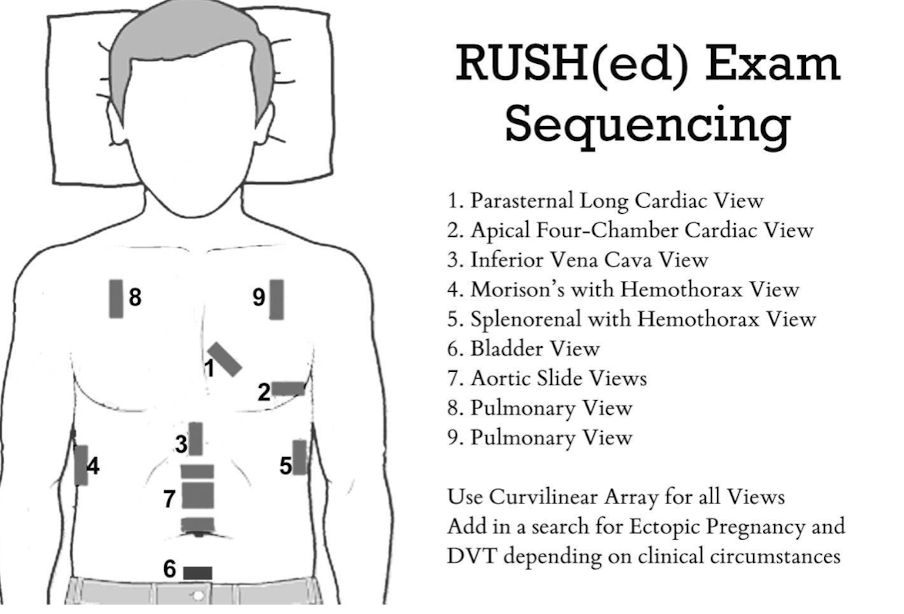

E-FAST (Extended Focused Assessment with Sonography in Trauma)

bedside ultrasound protocol design to detect peritoneal fluid, pericardial fluid, pneumothorax and/or hemothorax in trauma patient

RUSH Exam

ultrasound to quickly assess any patient with undifferentiated shock and hypertension